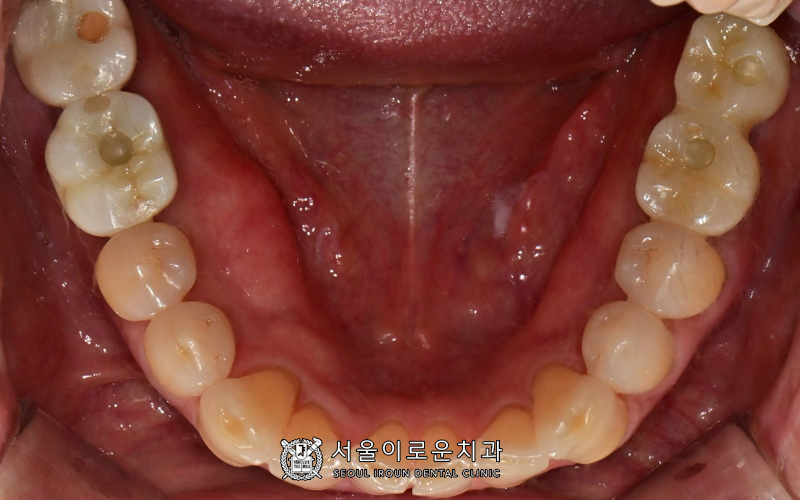

구강 내 사진을 보시겠습니다. ^^

환.자분의 경우

과거 타병원에서 아래 임플란트를 하신

치료이력이 있으셨는데요.

위에 치아가 상실된 후

아래 인공치와 맞물리는 치아가 없어

사실상 그간

임플란트를 사용하지 못하고 계셨습니다.